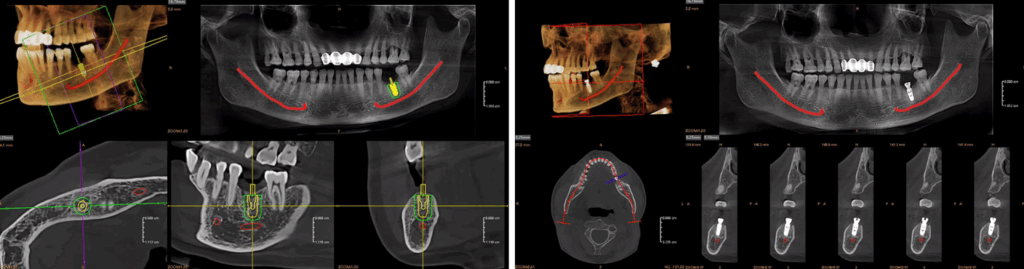

DES MIDES PANORAMIQUES POLYVALENTS POUR TOUS LES BESOINS CLINIQUES

5 x 5 cm

9 x 9 cm

12 x 10 cm

OPTIONS EXCLUSIVES DE CHAMP DE VISION DU RUBIK X3

16 x 11 cm

18 x 13 cm

18 x 20 cm